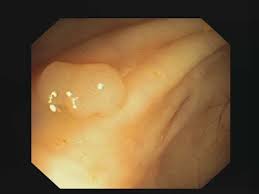

1) 비선종성 용종

대부분 매끈한 표면과 작은 크기를 가지고 있으며, 장 표면에 작게 솟아오르는 형태를 띱니다. 색이 정상 점막과 비슷하며 경계가 뚜렷합니다.

과형성 용종은 굉장히 작은 크기로 발견되며 암으로 발전할 가능성은 거의 없습니다. 내시경으로 쉽게 발견되고 제거가 간단합니다.